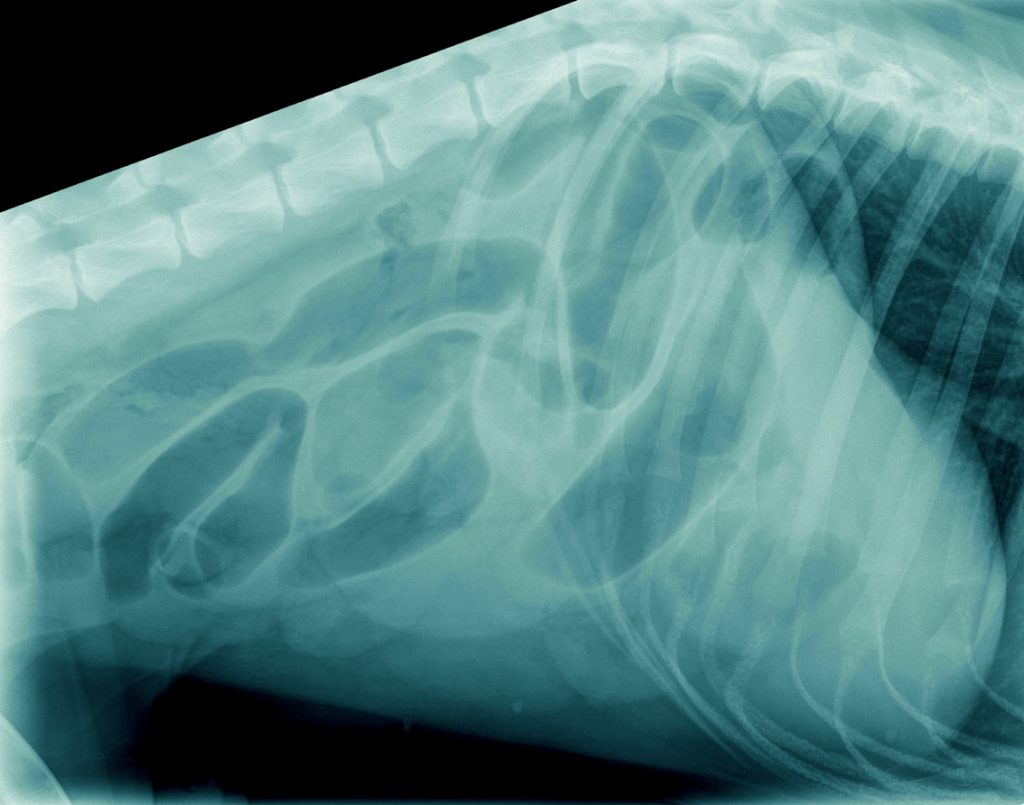

Op het spreekuur kwam T-Bone, een Duitse Herder reu van 1 jaar oud uit Tiel, die sinds een week wat slechter at, af en toe wat braakte en diarree vertoonde. Ondanks medicatie tegen overgeven bleef hij braken en na een paar dagen had hij geen ontlasting meer, alleen wat brij. Dit was reden om opnieuw naar de dierenarts te gaan. De röntgenfoto’s, die gemaakt werden, lieten veel lucht in het maagdarmkanaal zien. Dit kan onder andere wijzen op een verstopping.

Omdat de hond verder niet ziek was en de buik niet gevoelig, werd besloten om de röntgenfoto’s na een dag te herhalen. Hierop was er geheel geen verbetering zichtbaar in de buik ten opzichte van de dag ervoor.